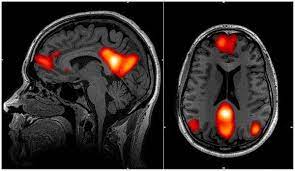

Previous studies, using functional MRI (fMRI) brain scanning, have shown that psilocybin seems to reduce activity in the medial prefrontal cortex, an area of the brain that helps regulate a number of cognitive functions, including attention, inhibitory control, habits and memory.

The compound also decreases connections between this area and the posterior cingulate cortex, an area that may play a role in regulating memory and emotions.

An active connection between these two brain areas is normally a feature of the brain’s “default mode network”. This network is active when we rest and focus internally, perhaps reminiscing about the past, envisioning the future or thinking about ourselves or others.

Just one day after the first dose of psilocybin, fMRI measures revealed an overall increase in connectivity between the brain’s various networks, which are typically reduced in those with severe depression. The default mode network was simultaneously reduced, while connectivity between it and other networks was increased – backing up previous, smaller studies.